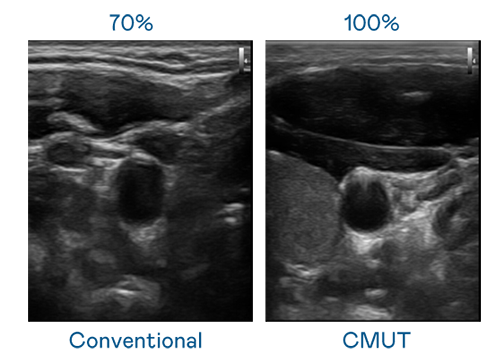

CMUT 技术是一种用电容式微机电元件来产生超音波讯号的技术。与传统 PZT 压电式技术相比,CMUT 频宽增加 30%,更宽频的超音波讯号让影像解析度大幅提升,是实现高影像品质医疗超音波扫描、促进精准医疗发展的关键技术。

大频宽带来超清晰影像

超音波影像的解析度高低,首先取决于探头能发出的讯号频宽。蘑菇mogu3官网入口更新 CMUT 可提供高清晰的超音波讯号,提供高频宽、高灵敏度、影像纹理细节更高的超音波影像,协助医护人员缩短影像判读时间及利用精准的医疗影像进行诊断。